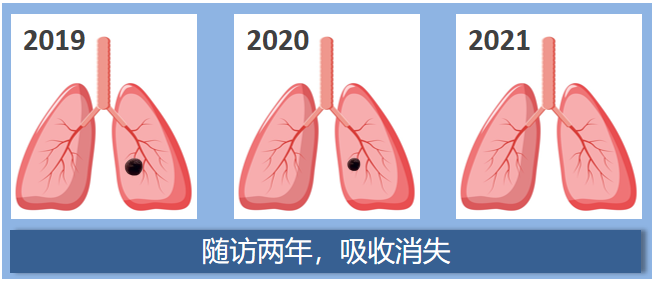

这是大家最关心的事了,我们来看几组肺结节随访病例模式图。

第一组:实性结节

患者2:2019年左肺发现一枚实性肺结节,两年的CT复查,肺内的这枚实性结节逐渐变小至消失不见了。